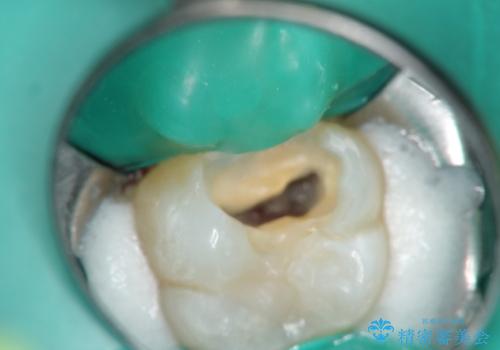

Bio-C Sealerを塗布後、神経に優しい光重合型充填用レジン強化グラスアイオノマーセメントで裏層を行っています。

※術前に神経の状態の検査を行い、術中にもマイクロスコープにて神経の状態を直接確認したうえで残せると判断した場合に行っています。

術中は唾液が入らないようラバーダムシートをかけています。